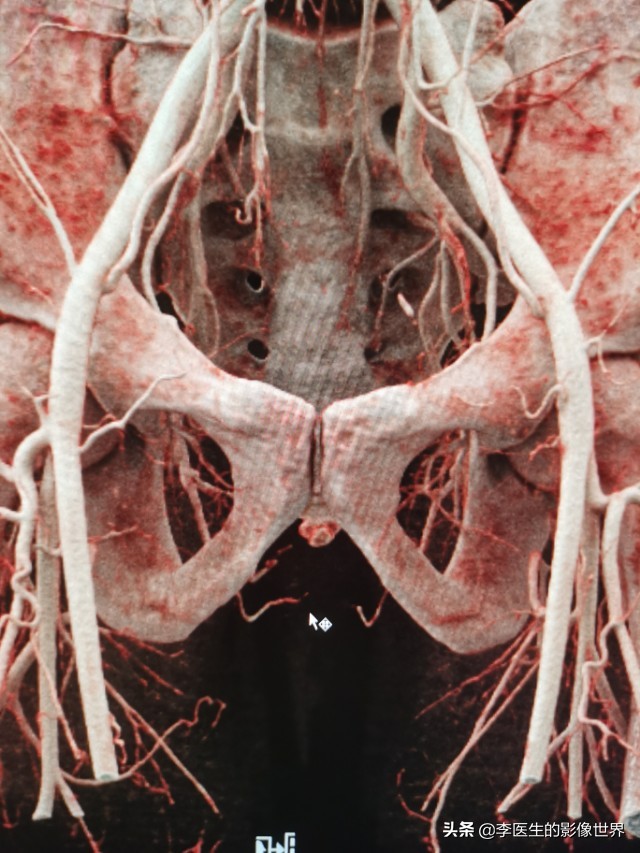

为临床诊断、手术方案制定提供便利。以下为阴部内动脉CT血管成像MIP、VR图。仅供交流。

冠状位VR显示

右侧阴部内动脉显示清晰,分出YJ动脉、会阴动脉。

鼠标所指左侧YJ动脉狭窄、显示不清。